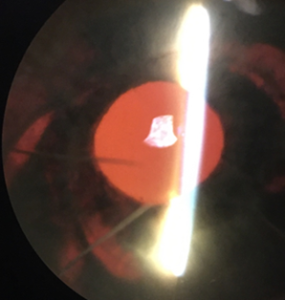

By day 13, 3+ cell remained (including RBCs) OD but flare decreased to a grade of 1+, allowing visualization of the iris and appreciable midperipheral circumferential transillumination defects (TIDs) at 1:00-4:00, 6:00-7:00, and 9:00-10:00, and no neovascularization of the iris (Figure 2). The PCIOL was present but flush with the iris. Gonioscopy revealed angles open to ciliary body 360 degrees OU with 1+ pigment in the trabecular meshwork OU, flat iris approach OU, and no evidence of neovascularization of the angle, angle recession, or peripheral anterior synechiae OU. The view to the retina OD remained hazy, but no appreciable vitritis or vitreous hemorrhage was noted. All anterior segment findings OS were within normal limits.

![]() Figure 2. Retro-illumination of the iris of the right eye on day 13: Circumferential transillumination defects 1-4:00, 6-7:00, and 9-10:00 are appreciable. They follow the shape of the IOL optic and haptics. Click to enlarge |

The patient was instructed to continue atropine 1% twice a day OD and timolol 0.5%/dorzolamide 2% twice a day OU. He was informed that he no longer needed to maintain a 45-degree incline but was advised to return to the clinic if redness or discomfort returned. The carotid ultrasound was completed and did not reveal any significant or asymmetric stenosis, ruling out ocular ischemic syndrome (OIS) as a diagnosis. Improved visibility of the iris confirmed lack of iris neovascularization, reducing the likelihood of neovascularization due to retinal vascular occlusion. However, because the fundus remained obscured, retinal vascular occlusion could not be definitively eliminated. Retro-illumination of the iris allowed visualization of significant iris TIDs, indicating mechanical interaction between the posterior iris and the PCIOL. Anterior segment optical coherence tomography (OCT) was used to confirm that the PCIOL was displaced anteriorly and interacting excessively with the iris (Figure 3a and 3b), supporting the diagnosis of UGH syndrome. The patient was referred to ophthalmology for evaluation of the IOL.

In this case and many others, TIDs can provide helpful clues in diagnosis of UGH syndrome. TIDs after cataract extraction are common, but pattern and location can differ based on cause. In contrast with pupillary margin TIDs caused by surgical instruments during cataract extraction, circumferential shape and mid-peripheral location of TIDs indicate chafing of the IOL optics and haptic on the posterior iris. This unique pattern is indicative of excessive PCIOL interaction with the iris and is frequently seen in UGH syndrome.5